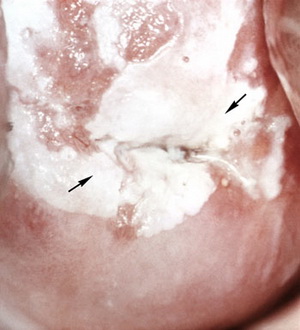

При кольпоскопии выделяют три формы лейкоплакии шейки матки:

- плоская лейкоплакия – белесоватые участки находятся на одном уровне с нормальным многослойным плоским эпителием;

- бородавчатая лейкоплакия – поверхность шейки матки выглядит бугристой за счет наслоения пораженных участков друг на друга и возвышения их над поверхностью;

- эрозивная лейкоплакия – при кольпоскопии помимо лейкоплакии на шейке матки в пораженной зоне определяются эрозивные участки или трещины.

По гистологическому заключению выделяют простую лейкоплакию шейки матки (или без атипии) и лейкоплакию с атипией .

Простая лейкоплакия характеризуется утолщением базального и зернистого слоя многослойного плоского эпителия и явлениями паракератоза.

Лейкоплакия с атипией относится к предраковым заболеваниям и заключается в появление базально-клеточной гиперактивности и атипичных клеток. В 15-75% случаев она может переходить в преинвазивный плоскоклеточный рак.